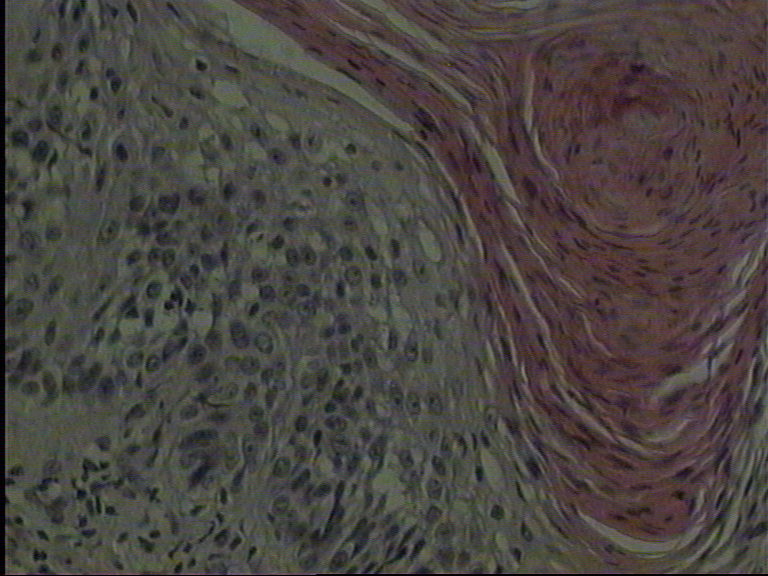

| Fig 1b:

Histology: Squamous cell carcinoma with a total depth of 0.7 mm.

Orthohyperkeratosis, epidermal hyperplasia with disturbance in the cell

arrangement of the lower epidermal layers associated with cellular and

nuclear polymorphism. Proliferation of atypical epithelial growth in the

upper dermis was seen (hematoxylin and eosin). |